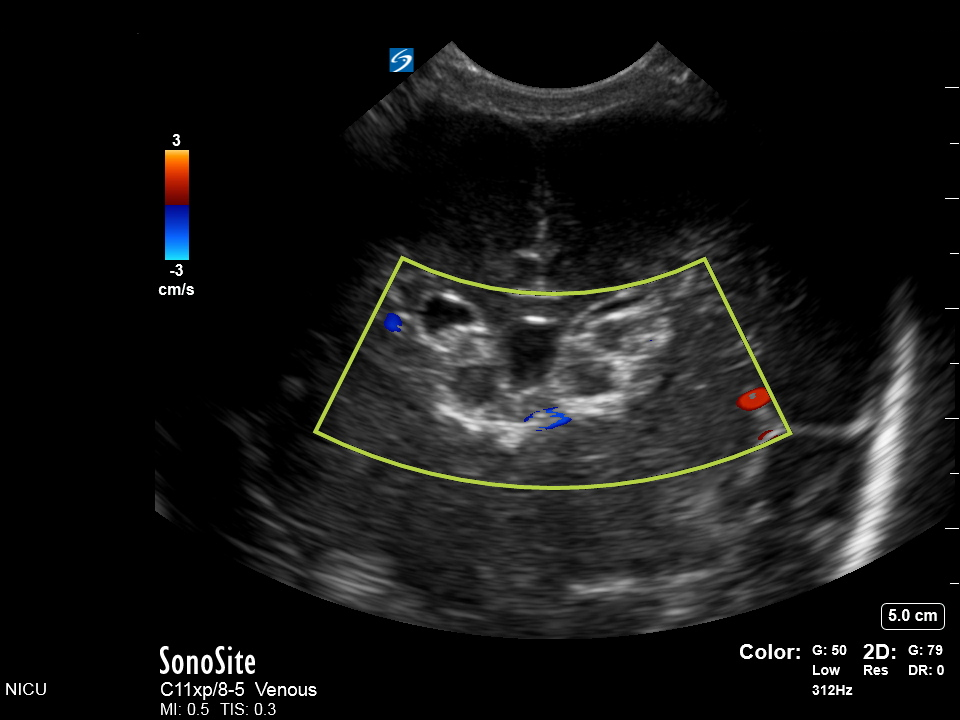

Neonatology Circle of Willis IVH Doppler Image